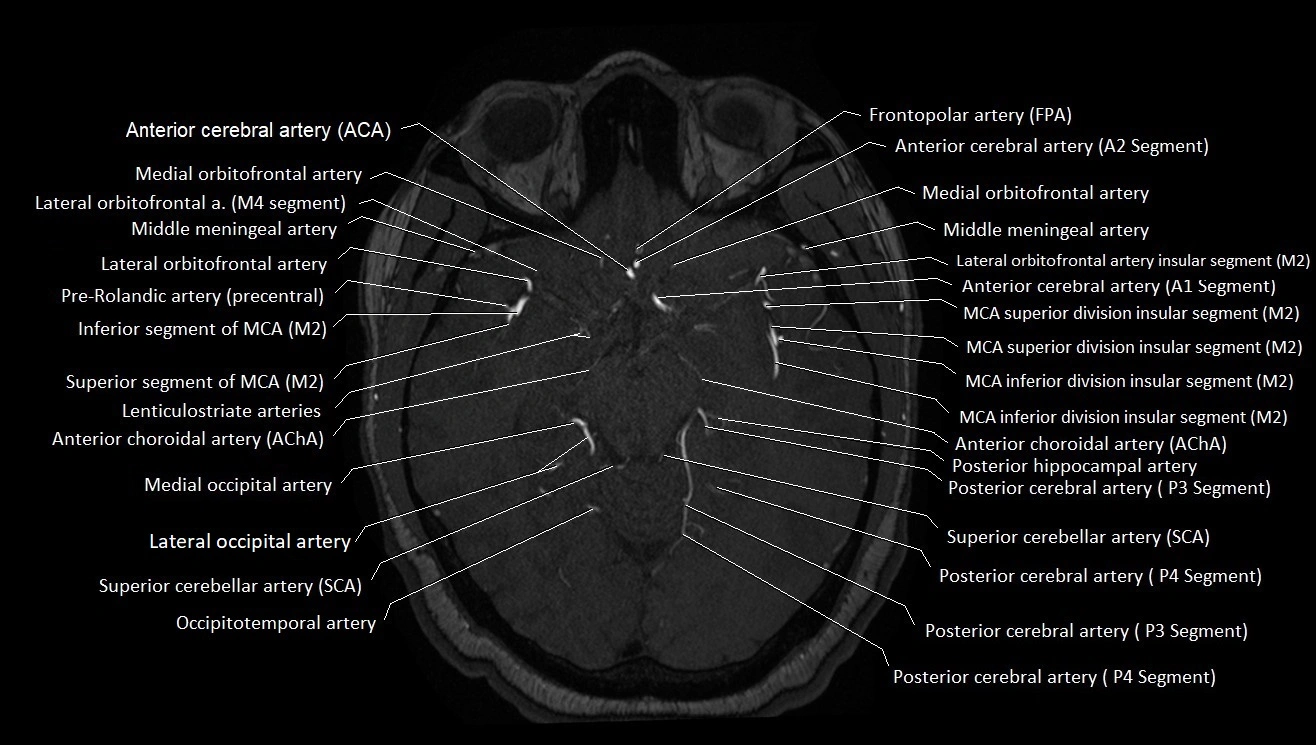

MRA (Magnetic Resonance Angiography):

• Flow-related enhancement makes the AChA appear as a bright, linear vascular signal against suppressed background

• High sensitivity for origin and proximal course; distal branches may be too small to resolve

• Detects stenosis, occlusion, aneurysm, AVM feeders

MRI images

image